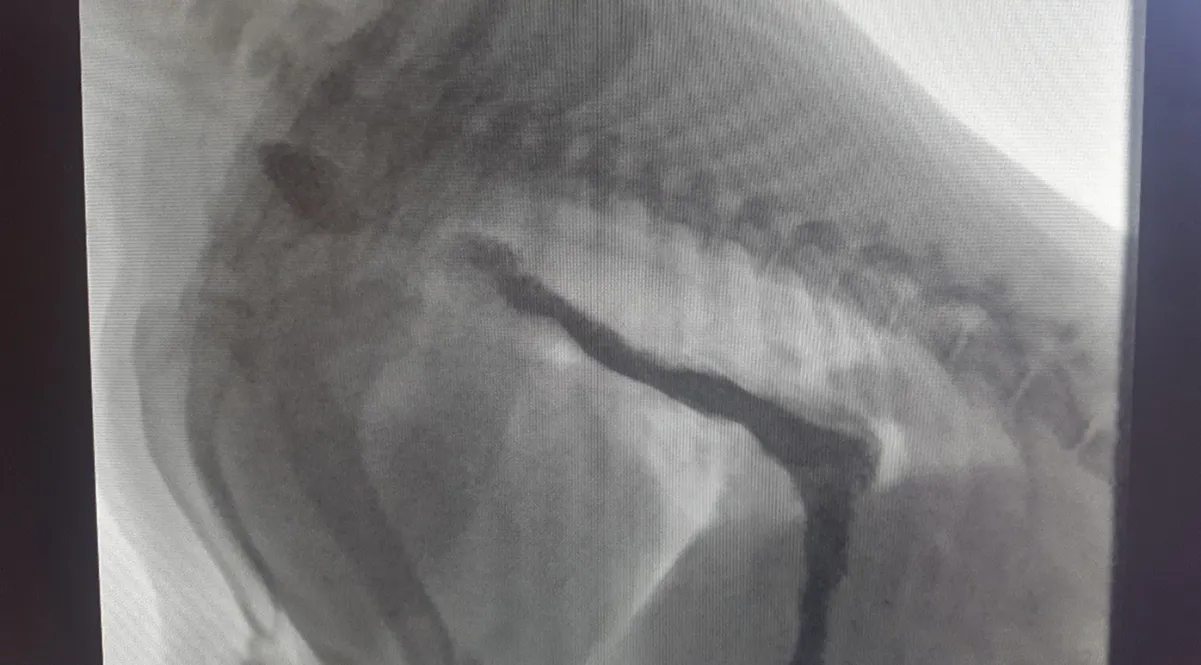

In a live fluoroscopy image, contrast appears black as it moves through the food pipe.

In addition, we can perform radiography in “real time”, which is called dynamic digital radiography (also known as fluoroscopy). This allows us to visualise certain processes as they happen in the patients. This approach is particularly valuable during the evaluation of dogs and cats with swallowing difficulties (dysphagia), regurgitation or other signs of oesophageal disorders.